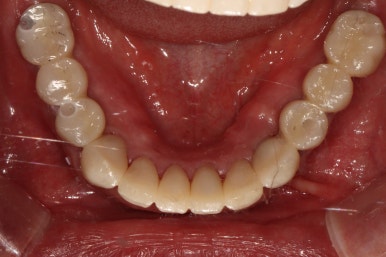

왼쪽: 위턱, 아래쪽: 아래턱

아래턱은 보시다시피 치아가 5개 밖에 남지 않았어요.